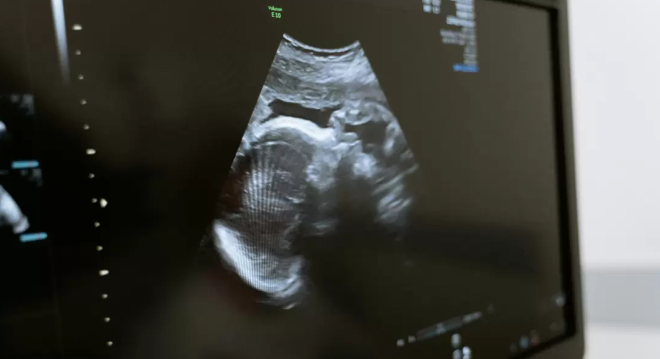

En el tercer trimestre de gestación, las participantes embarazadas se sometieron a una neurosonografía transvaginal, una ecografía avanzada que permite examinar con detalle la morfología y las estructuras del cerebro fetal.